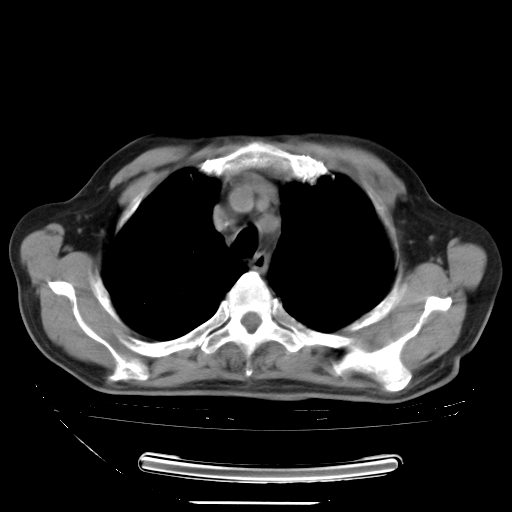

今天复查肺部CT,发现双肺广泛磨玻璃样改变。所以我把3月19日和5月9日相隔50天的肺部CT上传。请大家会诊。

2009年3月19日肺部CT片。

5月9日肺部CT(在4月27日齐鲁医院肺部CT描述部分肺组织磨玻璃样改变,12天后肺组织广泛磨玻璃样改变)

大致读了系列胸部CT:纵隔窗无明显异常,肺窗:从4、27至今:主要是双肺中下野外带可见毛玻璃样改变,目前处于急性肺泡炎阶段,至于原因考虑1、结替组织或胶原血管性疾病所致?2、恶性疾病如恶组在肺部所致的表现或细支气管肺泡癌?3、药物或其它原因如肺蛋白沉着症所致肺泡炎目前不太可能?总之,明天就去请我院的呼吸科、感染科、血液科和临免专家会诊哈。